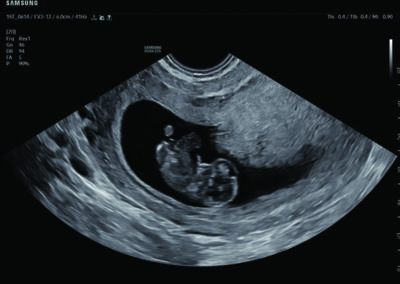

Comprehensive, advanced and expert MFM care for high-risk pregnancies

- Fetal anomalies